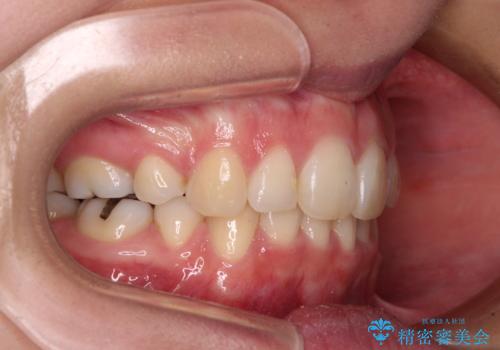

デコボコで飛び出した前歯 ワイヤー装置による抜歯矯正

- 上下前歯のデコボコと、飛び出した前歯を気にして来院された患者様です。

口元を積極的に引っ込めるために、上下左右の小臼歯計4本を抜歯することとしました。

咬み合わせが深く、咬合力強いため、補助装置を使用しながら積極的に口元を下げることとしました。

矯正治療前の咬み合わせで、前歯がすり減ってしまい、歯列が整ったときに先端がガタガタになってしまったため、矯正治療後に形態修正を行いました。